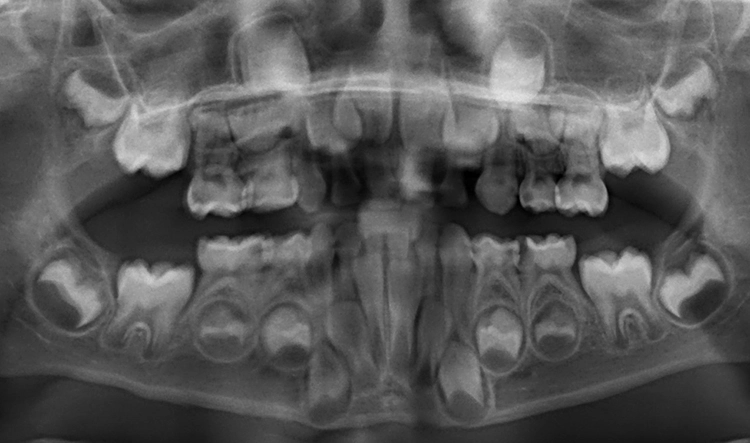

Ein 4-jähriges mäßig kooperatives Kind erscheint zur Kontrolle in der Zahnarztpraxis. Bei der klinischen Untersuchung sind offensichtlich zwei (scheinbar kleinere) approximal kavitierte kariöse Läsionen im Unterkiefer zu sehen sowie Läsionen an den Oberkieferschneidezähnen (Abb. 1a und b). Eine Versorgung dieser Zähne scheint nach klinischer Untersuchung bei diesem Kind noch ambulant möglich.

Erst eine weitergehende röntgenologische Untersuchung zeigt das ganze Ausmaß des Kariesbefalls (Abb. 1c). Das Kind wies an fast allen Milchzähnen bereits Dentinkaries, zum Teil auch schon sehr tiefe Läsionen (Zahn 75), auf. Solch ein Befund scheint bei zahlreichen konventionell-restaurativen Maßnahmen bei altersentsprechender mäßiger Kooperation (fast) nur in Narkose behandelbar.

Dieser Fall führt deutlich vor Augen, dass die richtige Diagnosestellung anhand adäquater Diagnostik die Basis jeder Therapieentscheidung darstellt. Der vorliegende Beitrag betrachtet im Schwerpunkt die Kinderzahnheilkunde, wobei die beschriebenen aktuellen Konzepte im Bereich der Untersuchung von Karies und der kariesspezifischen Risikoeinschätzung – also insbesondere der Diagnostik – nicht nur für „Kinderzähne“ gelten. Das Verständnis von der Erkrankung „Karies“ und das Wissen zu verschiedenen Optionen in der Kariesdiagnostik stellt die Grundvoraussetzung für die korrekte Diagnose dar und folglich auch für „modernes“ Kariesmanagement.